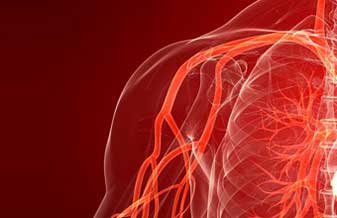

- Whatsapp Mulatti Reinaldo Angiologista Doenças Vasculares

- Suporte Mulatti Reinaldo Angiologista Doenças Vasculares

- Atendimento Mulatti Reinaldo Angiologista Doenças Vasculares

- SAC Mulatti Reinaldo Angiologista Doenças Vasculares

- Contato Mulatti Reinaldo Angiologista Doenças Vasculares